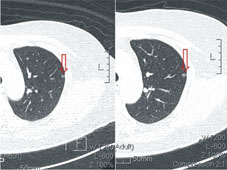

目前所知的胸部檢查中,電腦斷層可以提供比傳統胸部X光檢查更詳細的影像,能夠更清楚看到更小的腫瘤,也不會被心臟及骨頭擋住。但是電腦斷層自1974年問世以來,卻為何遲遲無法作為肺癌篩檢的工具?最主要是因為檢查所帶來的輻射量過大。我國原子能委員會參照國際原子能總署提出的建議,一般民眾每年接受的劑量限值(不含背景輻射及必要醫療劑量)為1毫西弗,輻射工作人員則為20毫西弗。而一般胸部電腦斷層一次檢查需接受5-7毫西弗,在衡量效益及輻射副作用後,無法使用在肺癌篩檢。然而隨著科技的進步,目前新的多切式電腦斷層大幅降低每次檢查所接受的輻射量,一次低輻射劑量胸部電腦斷層僅有0.3-0.8毫西弗,相當於4-10張胸部X光檢查,就可以提供等同於過去電腦斷層的影像,若再配合電腦輔助檢測軟體,協助分析數位化電腦斷層胸腔影像,發現、鑑定以及評估肺部結節,可以提高直徑5-8 mm的小型結節的檢出,使肺部疾病可以提早發現,及早治療。(如:圖一)

圖一

一位50歲女性 圖左箭頭所示為2014年2月低輻射胸部電腦斷層顯示一約0.5公分結節。圖右為2014年5月追蹤發現該結節有略為變大。於6月切除,證實為第一期肺癌